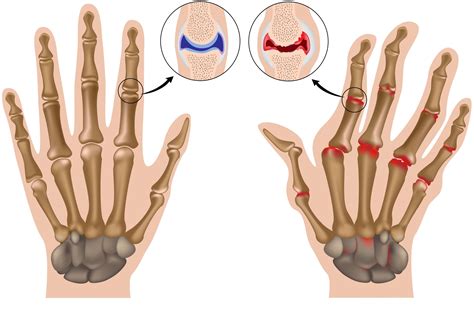

Anatomy of hand joints prone to arthritis

Arthritis is not a single disease but rather a general term for joint inflammation. When it comes to arthritis in hand, it typically manifests in the joints of the fingers, the knuckles, or the base of the thumb. The two most common types that affect the hands are osteoarthritis (OA) and rheumatoid arthritis (RA).

• Osteoarthritis (OA): Often called "wear-and-tear" arthritis, this occurs when the protective cartilage that cushions the ends of the bones wears away over time. It is the most common form and is usually age-related.

• Rheumatoid Arthritis (RA): This is an autoimmune disorder where the body's immune system mistakenly attacks its own tissues, specifically the lining of the joints (synovium). This leads to painful swelling, inflammation, and can cause severe joint deformity if left untreated.